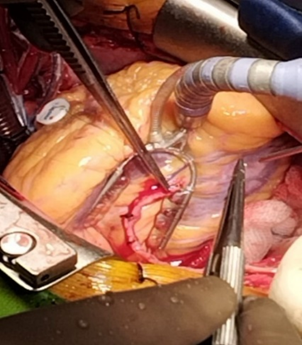

The patient was denied to do Intravascular Ultrasound (IVUS) and Fractional Flow Reserve (FFR) assessment. So, after evaluation of the patient, he was sent to the operating room for coronary artery bypass surgery with unroofing of myocardial bridge in mid LAD. Surgery was performed with endotracheal intubation under G/A and with median sternotomy. After median sternotomy, pericardiotomy was done. Aorta showed healthy, PA (Pulmonary Artery) showed mildly tense, LV-Normal. Cardiopulmonary Bypass was established with aortic and dual stage venous cannulation. At first on pump beating heart, RSVG (Reverse saphenous venous graft) to PDA, distal grafting was done with prolene 7/0.

Figure 8: RSVG to PDA graft.

Then aorta was cross clamped and heart was arrested with antegrade cold-blood cardioplegia. After that to inspect epicardial surface of heart for intramyocardial LAD, was easily detected. Epicardial incision was given over the normal site of LAD coronary artery with 15 size surgical blade. Then dissection was extended proximally into the bridging portion of LAD coronary artery with the dissection of epicardial fat and underlying muscle or myocardial bridge with the help of Potts scissors and Electrocautery. The length of the myocardial bridge was about 4.5 cm. Careful dissection was done to avoid damage to the LAD coronary artery and its branches such as diagonal artery and to avoid injury to right ventricle. During dissection of epicardial fat and outer part of myocardial bridge electrocautery or Liga clip were used for hemostatic purpose.

Figure 9: Surgical Unroofing of Myocardial Bridge with exposed LAD artery.